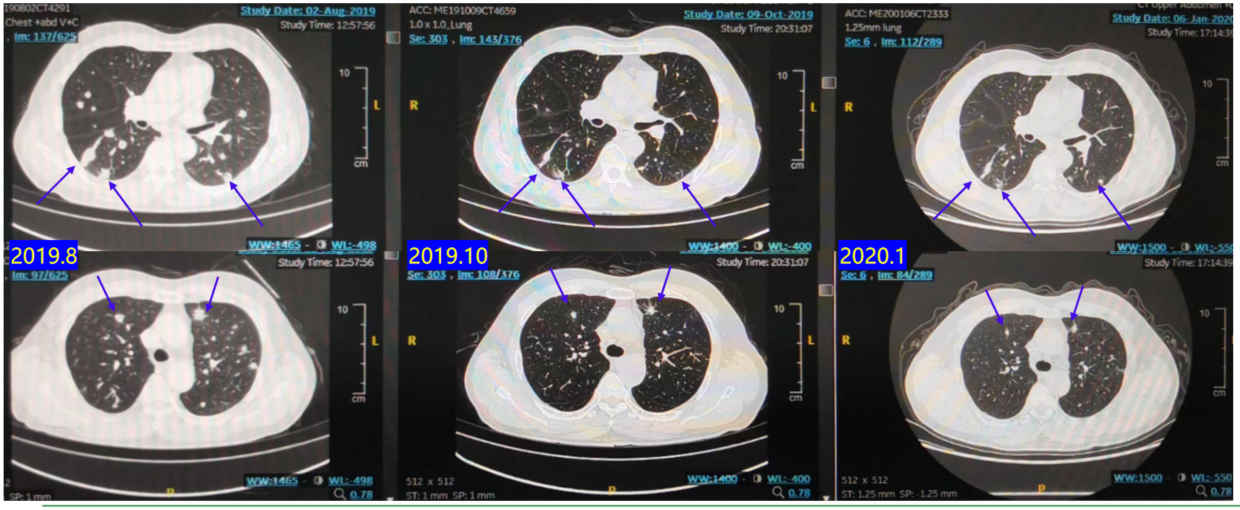

2019.08:复查CT提示肺部转移灶进展(图3),疗效评价为疾病进展(PD),PFS 12个月。

2019.08-2020.02:行西妥西单抗 + FOLFIRI 治疗10周期。

疗效评估:C4、C8评估为SD(图4),C10后评估为PD。PFS 7个月。

2020.03-2020.06:行贝伐珠单抗 + FOLFOX治疗4周期。

疗效评估:C4评估为PD(图5)。PFS 3个月。